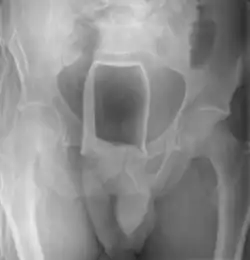

Vor dem Entfernen des Fremdkörpers werden meist radiologische Bilder in unterschiedlichen Projektionsebenen aufgenommen, um die genaue Lage und Tiefe des Fremdkörpers festzustellen. Dies geschieht in der Regel durch Röntgen. Bei Fremdkörpern aus Materialien, die einen zu geringen Kontrast im Röntgenbild liefern (beispielsweise Gegenstände aus massivem Kunststoff), kann gegebenenfalls auf Sonografie (Ultraschall) oder Computertomographie ausgewichen werden.[24] Die Magnetresonanztomographie ist insbesondere bei unbekannten Fremdkörpern kontraindiziert. In das Rektum eingeführte Fremdkörper können unter Umständen bis weit in das Kolon vordringen, in einigen Fällen bis zur rechten Flexur.[11]